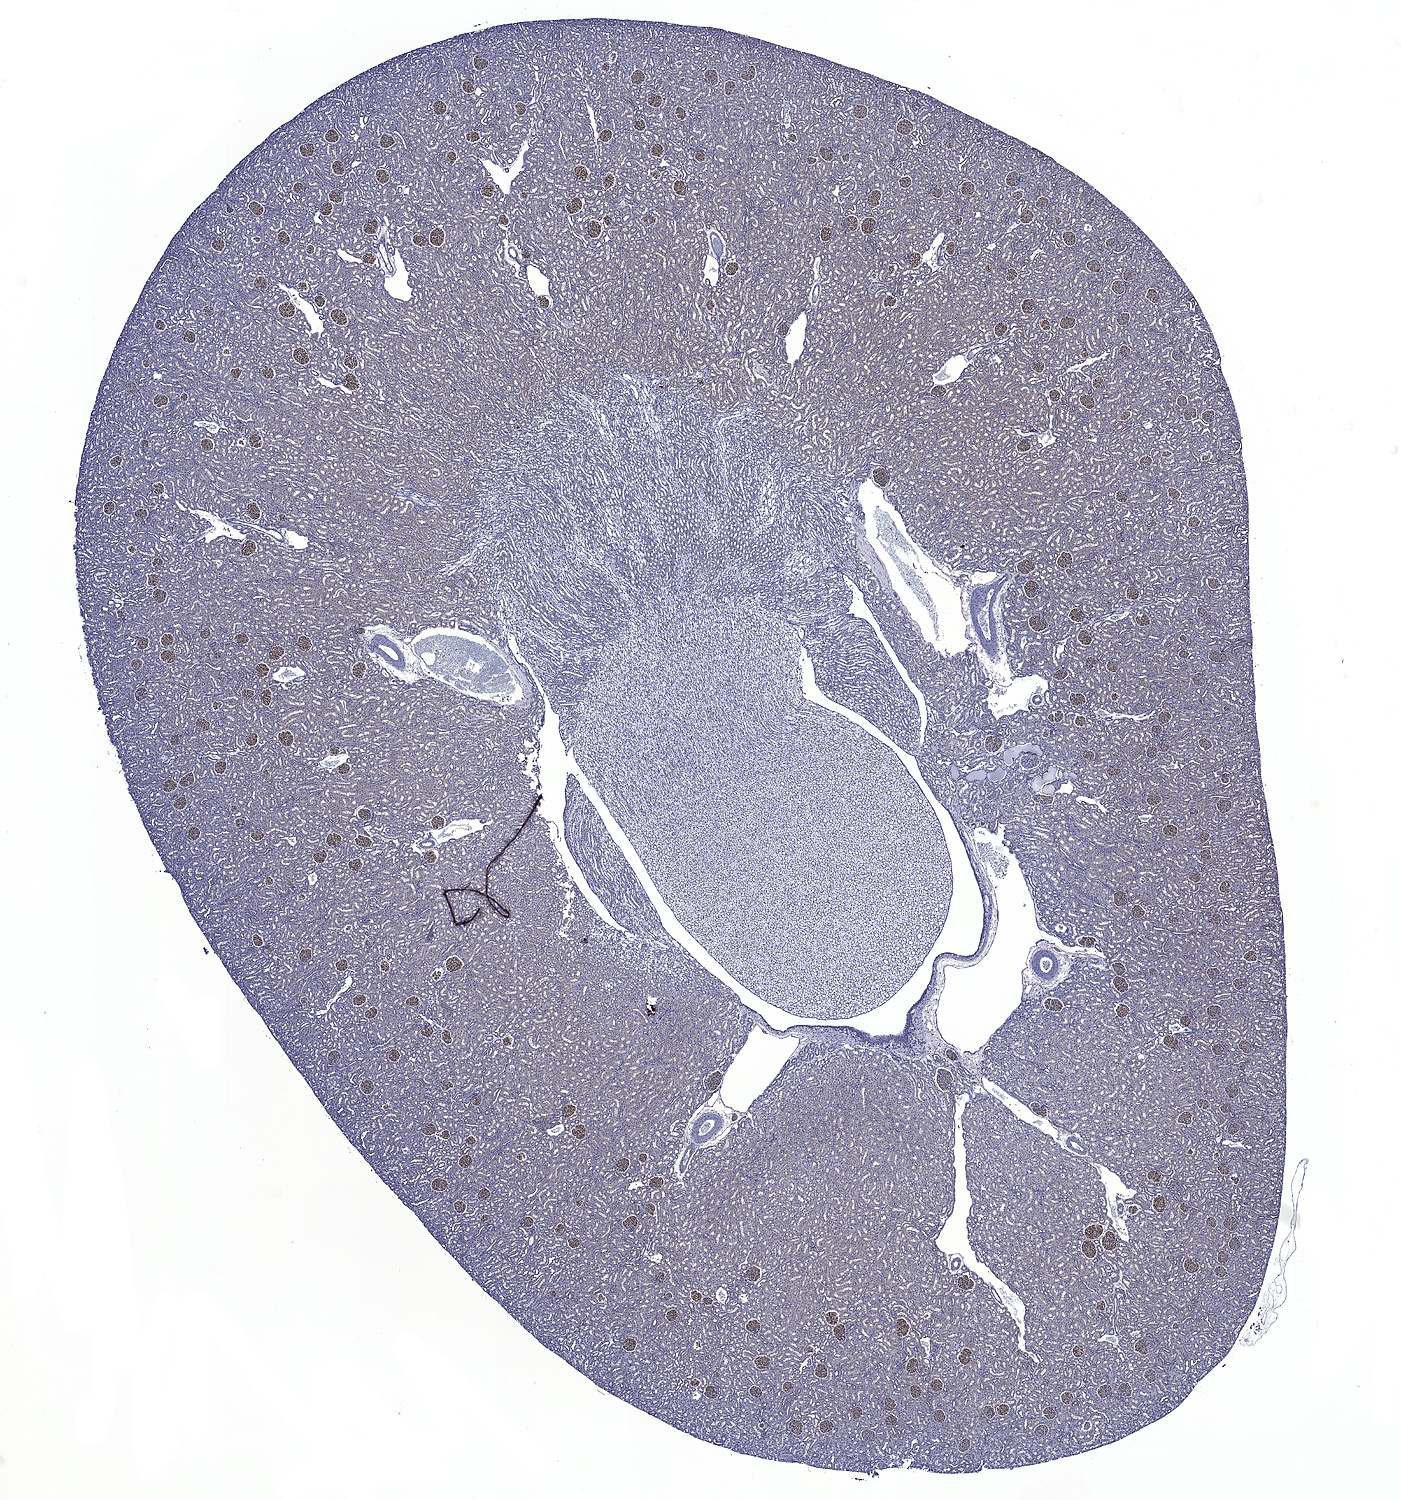

C3: Immunoperoxidase staining of formalin-fixed, paraffin-embedded rat kidney showing cytoplasmic staining in the glomeruli.